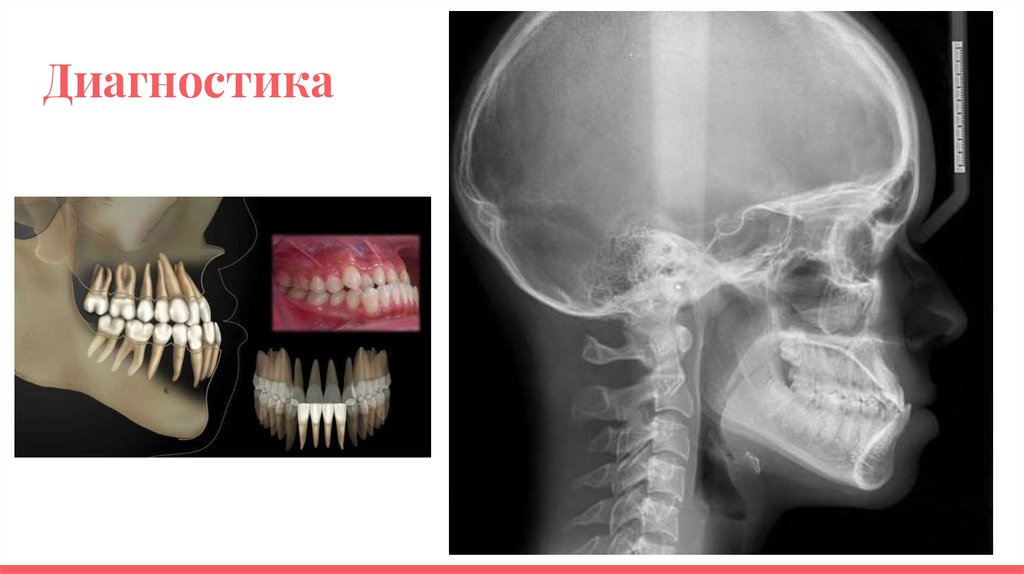

Диагностика